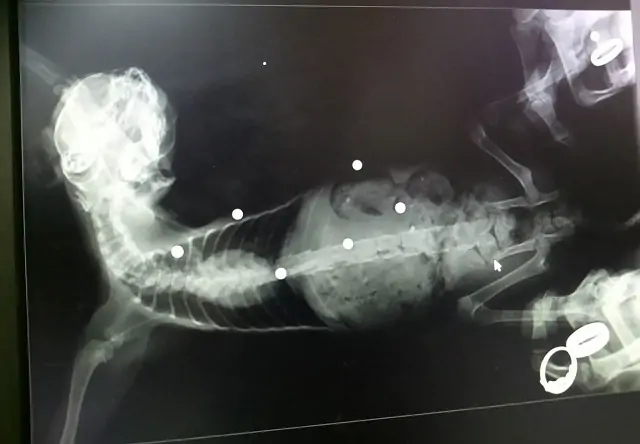

Как сообщили в местном отделении организации по защите животных «Доброе сердце», в кошку выстрелили 8 раз из пневматического газобалонного пистолета. Пули попали в глаз, позвоночник и задели внутренние органы.

Четвероногому предстоит операция по удалению некоторых пуль, но пулю из глаза ветеринары доставать не планируют, так как кот может не перенести операцию.